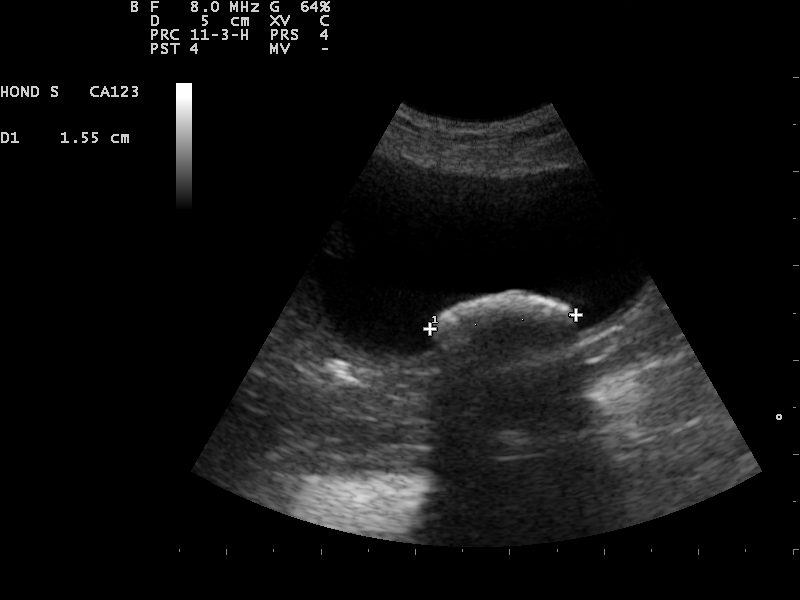

En dit bleek inderdaad het geval. In september van 2016 constateerde we, met behulp van een echo, weer nieuwe blaassteentjes bij Amy.

Ze waren nog wel heel klein, maar ze waren er wel weer. Ondertussen had onze dierenartspraktijk geïnvesteerd in allerlei scopen.